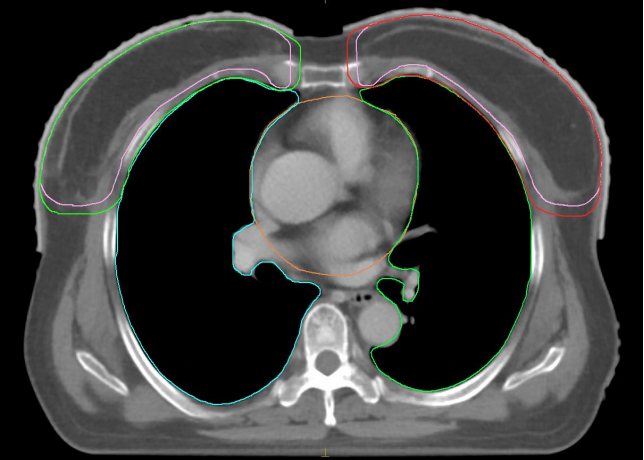

其次,为进一步降低心脏受照剂量,团队采用了深吸气屏气(DIBH)技术。通过训练,患者在深吸气状态下屏住呼吸,此时肺部扩张,心脏因生理解剖关系自然下移,远离放射区域,从而实现对心脏的“生理性保护”。这一主动屏气配合放疗,不仅显著降低了心脏辐射剂量,也减少了后期发生放射性心肌病、冠状动脉病变等并发症的风险。

DIBH技术:患者深吸一口气然后憋住,使胸廓和肺处于扩张状态,心脏移向后下方,心脏和肺组织主动“避开”高剂量辐射区照射。

在放疗技术选择方面,团队采用了兼具精准性与经济性的VMAT技术。VMAT通过治疗设备360度旋转,动态调节射线强度与照射角度,如“精准雕刻”般将剂量集中于肿瘤区域,同时最大限度规避正常组织,并大幅缩短了单次治疗时间。